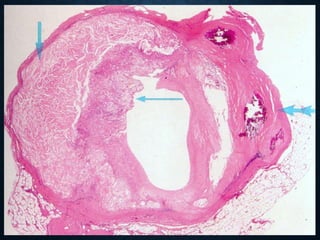

VASCULAR HYALINE

• it is located in the wall of small arteries

• thickening of the wall and narrowing of the blood vessel

lumen consists of precipitated plasma proteins that infiltrated

the wall under elevated hydrostatic pressure, in hypertension,

as well as elements of the endothelial basement membrane

(collagen type IV)

• Physiological hyalinosis in old age, primarily in the arteries of

the white pulp of the spleen

• in systemic hypertension

• diabetes mellitus (diabetic microangiopathy)